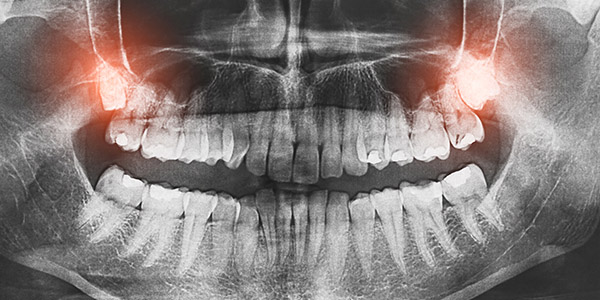

Wisdom teeth are the last molar teeth in your mouth. They usually erupt between the ages of 18-25.

Gum pain from wisdom teeth usually result from constant food packing and an accumulation of plaque around the gum. This can cause the gum to become inflamed and swollen. The resulting issue is constant pain, halitosis and pain that my radiate along your face or jaw.